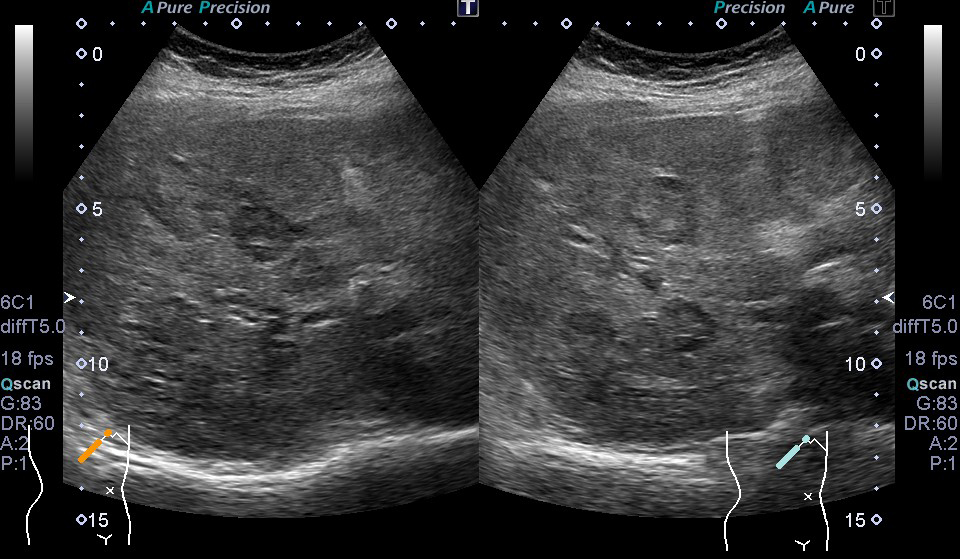

超音波(エコー) 診断画像

- 転移性肝がん

- 大腸がん

- 腎細胞がん